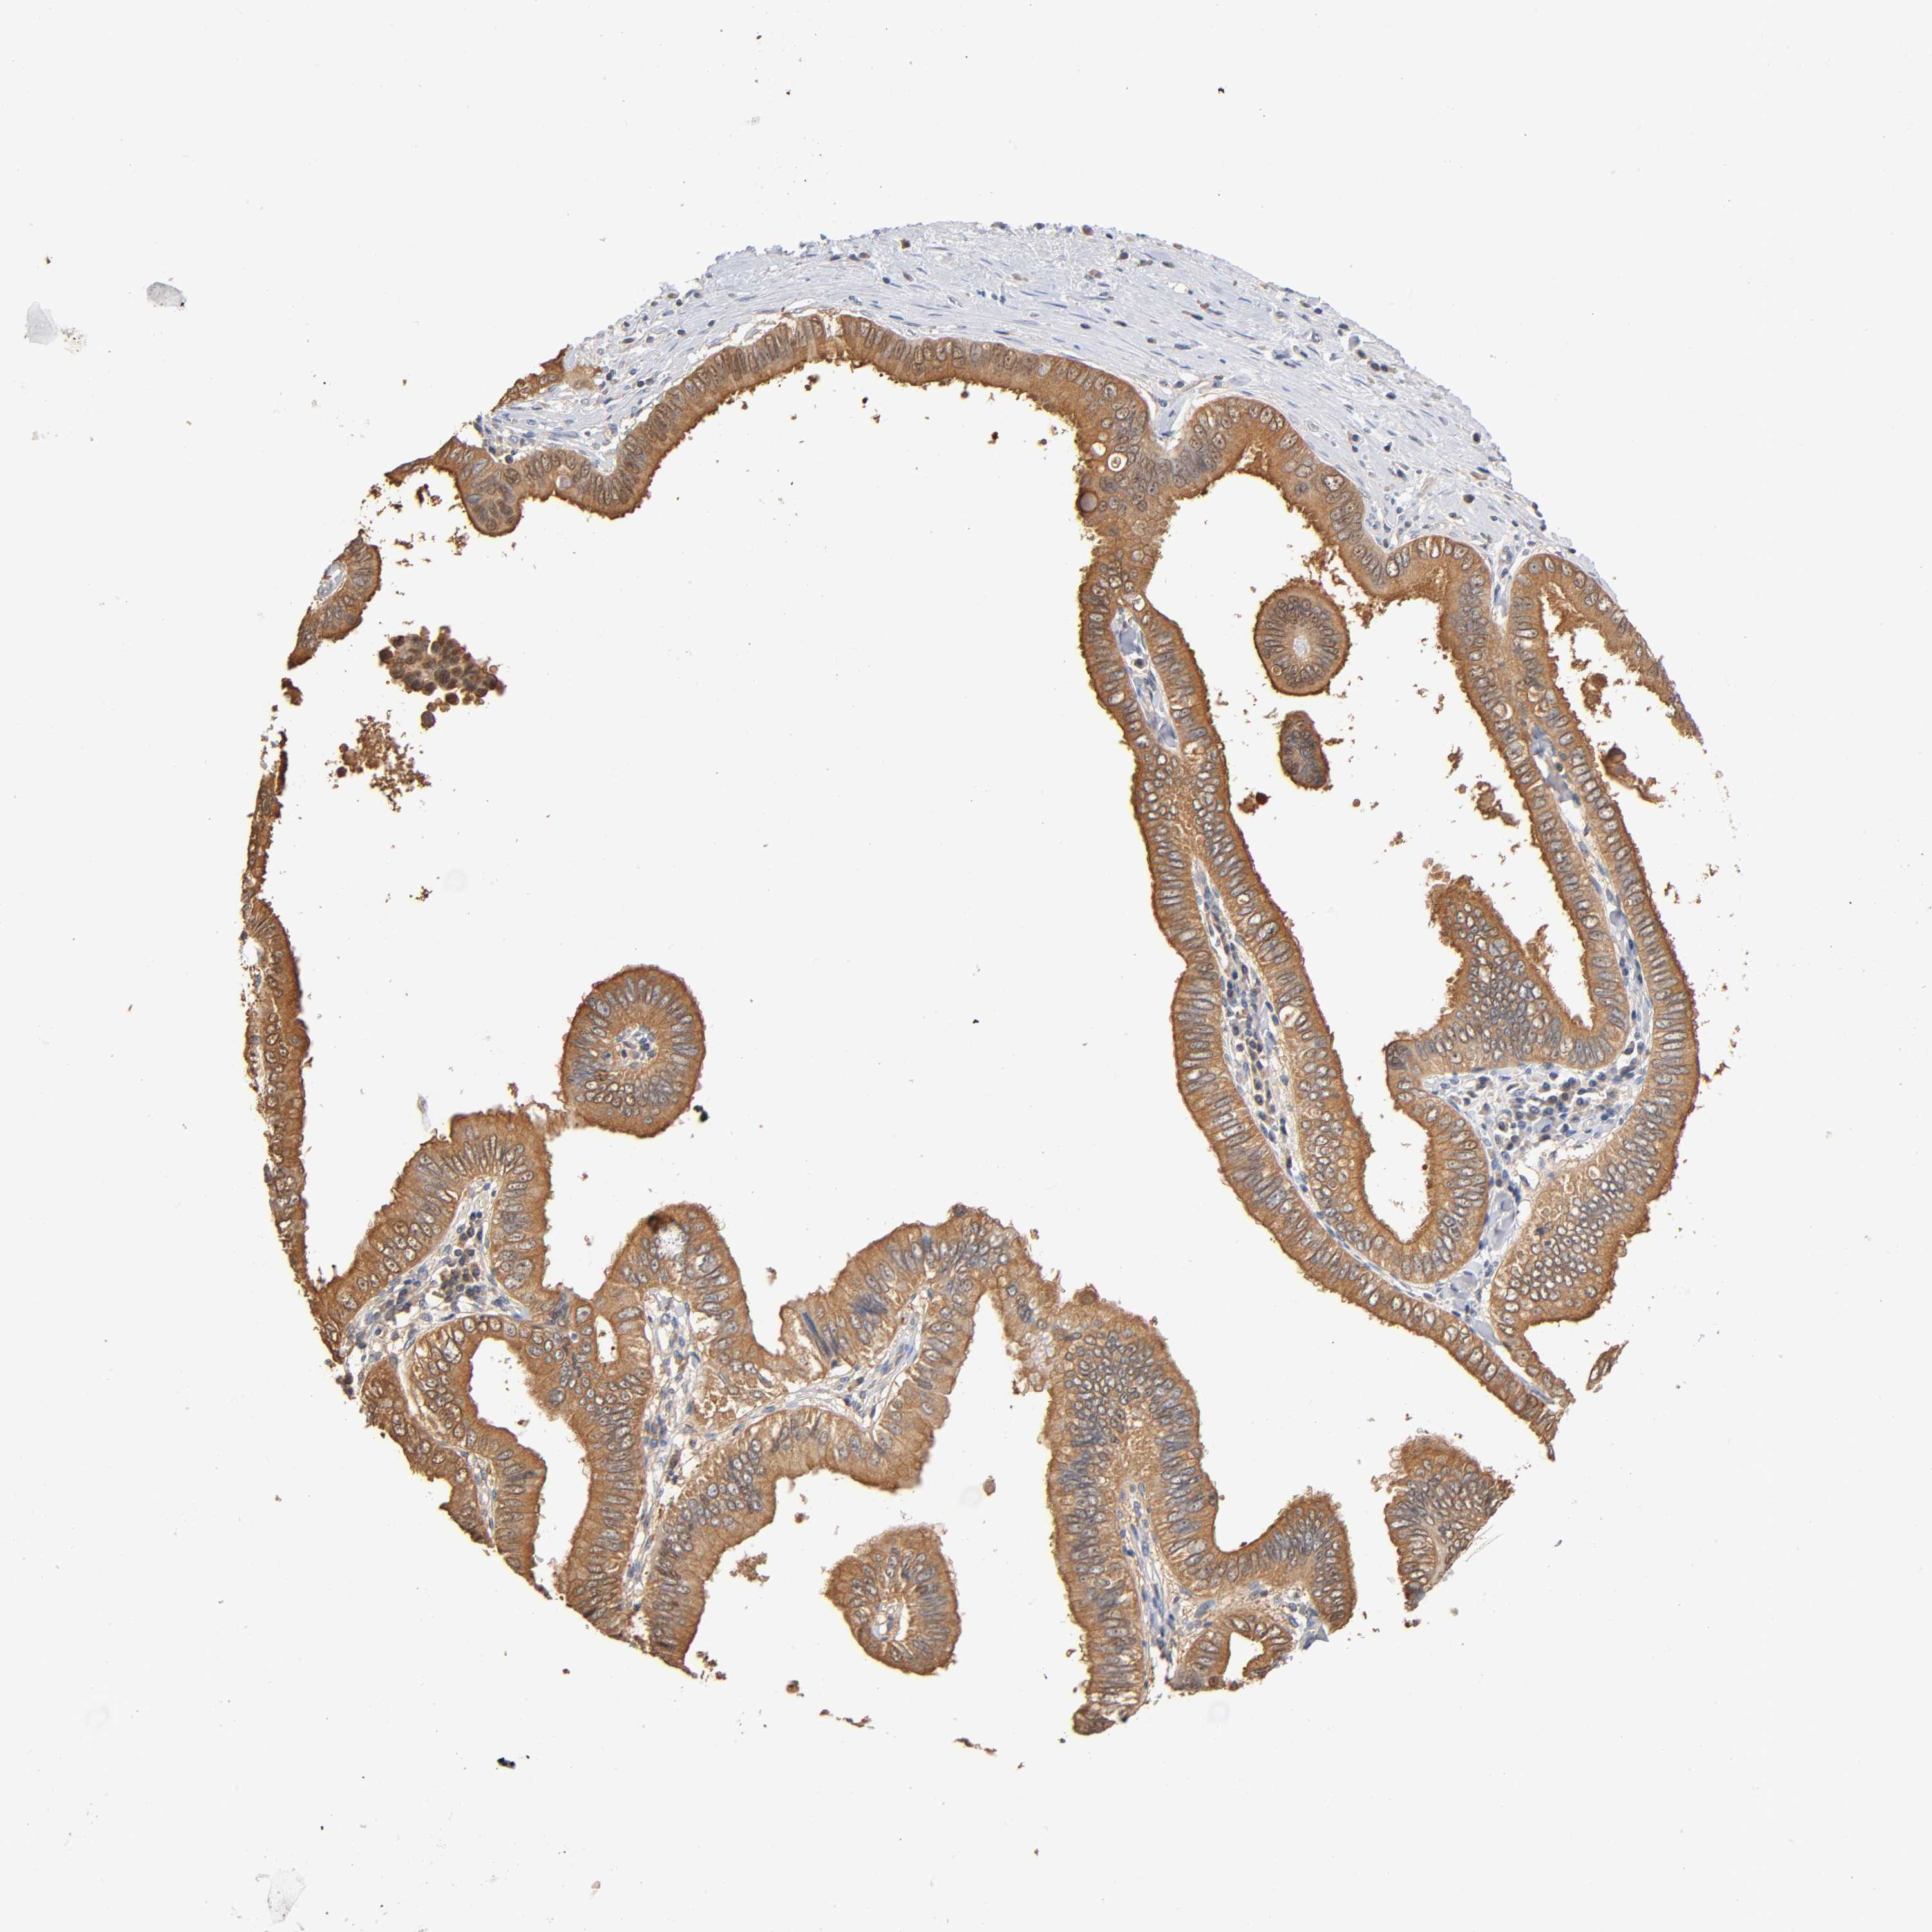

PANCREATIC CANCER - Protein expressioni

A mouse-over function shows sample information and annotation data. Click on an image to view it in a full screen mode. Samples can be filtered based on level of antibody staining by selecting one or several of the following categories: high, medium, low and not detected. The assay and annotation is described here.

Note that samples used for immunohistochemistry by the Human Protein Atlas do not correspond to samples in the TCGA dataset.

Antibody stainingi

Antibody staining in the annotated cell types in the current human tissue is reported as not detected, low, medium, or high, based on conventional immunohistochemistry profiling in selected tissues. This score is based on the combination of the staining intensity and fraction of stained cells.

Each image is clickable and will lead to virtual microscopy that enables deeper exploration of all samples and also displays staining intensity scores, fraction scores and subcellular localization as well as patient and tissue information for each sample.

Antibody HPA004177

Antibody CAB006252

Staining

High

Medium

Low

Not detected

Intensity

Strong

Moderate

Weak

Negative

Quantity

>75%

75%-25%

<25%

None

Location

Nuclear

Cytoplasmic/membranous

Cytoplasmic/membranous,nuclear

Adenocarcinoma, NOS

Adenocarcinoma, metastatic, NOS